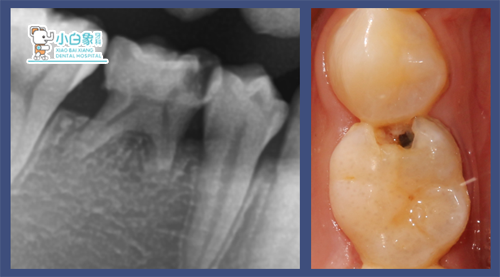

检查:85近中邻合面龋坏达髓角,叩(士),探(+++)温度试验敏感,牙龈无红肿。

诊断:85牙髓炎

治疗计划:85去髓术

治疗过程:在局麻下去腐质,开髓,清理根管,常规冲洗,隔湿干燥,根管内置Vt,磷酸锌垫底,纳米充填。

治疗前: